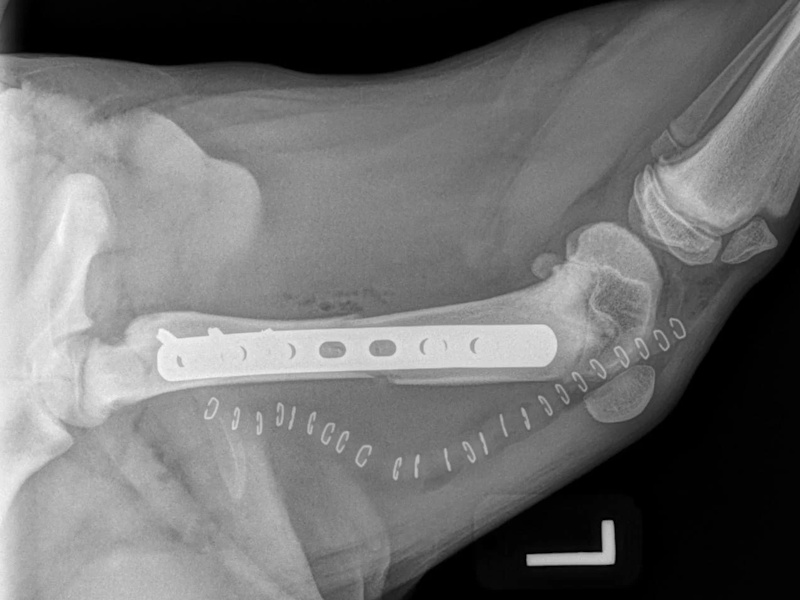

Tibial Plateau Leveling Osteotomy (TPLO) - additional information

An osteotomy is a surgical cut in a bone. In the cruciate deficient stifle, a cut is made in the top of the tibia. The top portion of bone that contains the articular surface is rotated to level it. The two pieces of bone are held in place with a metal plate and screws.

Post Surgical Radiographs

While the patient is still anesthetized, the patient is taken into radiology for post-surgery radiographs (X-rays). The radiographs are assessed to measure the new tibial plateau angle. We are aiming for 5-6 degrees relative to the long axis of the tibia. The apparatus (plate and screws) are assessed for size and appropriate position.